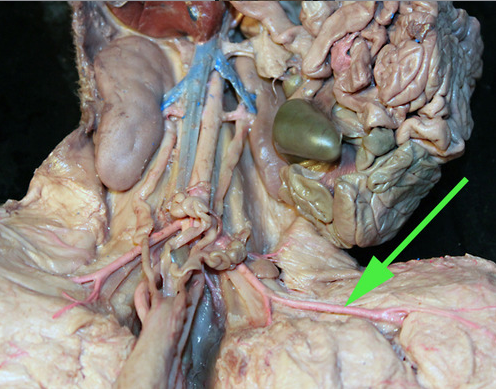

what is the green arrow pointing at? //abdominal aorta

In the area marked by the green arrow, the aorta is called the thoracic aorta